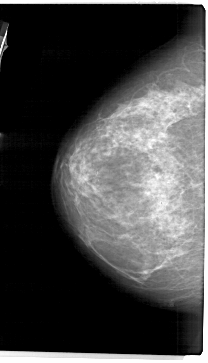

ics_version 1.0 filename A-1944-1 DATE_OF_STUDY 19 7 1994 PATIENT_AGE 72 FILM FILM_TYPE REGULAR DENSITY 3 DATE_DIGITIZED 8 7 1999 DIGITIZER HOWTEK 43.5 SEQUENCE LEFT_CC LINES 5431 PIXELS_PER_LINE 3106 BITS_PER_PIXEL 12 RESOLUTION 43.5 NON_OVERLAY LEFT_MLO LINES 5491 PIXELS_PER_LINE 3406 BITS_PER_PIXEL 12 RESOLUTION 43.5 NON_OVERLAY RIGHT_CC LINES 5116 PIXELS_PER_LINE 3046 BITS_PER_PIXEL 12 RESOLUTION 43.5 OVERLAY RIGHT_MLO LINES 5491 PIXELS_PER_LINE 3391 BITS_PER_PIXEL 12 RESOLUTION 43.5 OVERLAY |